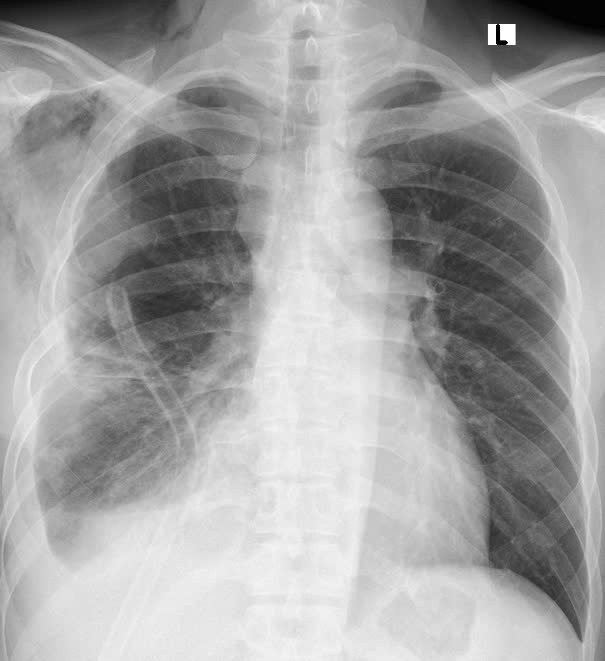

| Hình ảnh phim chụp X.quang trước và sau khi phẫu thuật. Hình trước phẫu thuật (bên trái): Khối u xâm chiếm khoang ngực, gây xẹp gần như toàn bộ phổi phải - Ảnh BVCC |

Qua thăm khám và chụp cắt lớp vi tính lồng ngực, các bác sĩ phát hiện khối u trung thất khổng lồ nằm lệch trong khoang màng phổi phải, chèn ép gây xẹp gần như toàn bộ phổi phải, đẩy lệch cơ hoành. Kết quả sinh thiết xác định đây là u bao sợi thần kinh Schwannoma - Một loại u lành tính hiếm gặp xuất phát từ bao thần kinh nhưng kích thước "khủng" hiếm thấy.